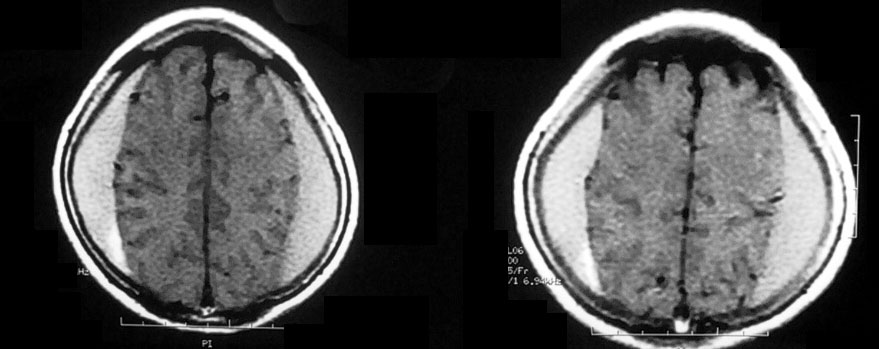

Медицинские аспекты и диагностика субдуральной гигромы мозга